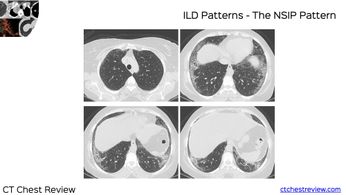

Case 115 - Ground Glass + Septal Thickening Paid Members Public

Ground glass plus septal thickening has a specific set of conditions that can be differentiated based on appearance morphology, presentation (acute/subacute/chronic) and presence of other findings in the chest or elsewhere on whole body scanning